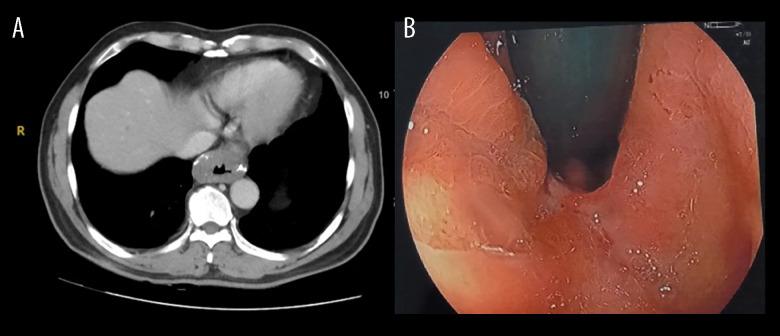

BACKGROUND Esophageal leiomyoma is a rare condition, with an estimated incidence rate of 0.4% of all esophageal neoplasms. These tumors are typically small, rarely more than 5 cm. The treatment depends on symptoms and the size and location of the tumor, with enucleation as the standard treatment of esophageal leiomyomas. Esophagectomy is performed only in very few cases, such as when the tumor is too large, there are multiple leiomyomas, there is a horseshoe shape or circumference, or the tumor is inextricably adhering to the esophageal mucosa. In such complex cases, it is often difficult to perform enucleation. However, with the risks of esophagectomy and intra-thoracic anastomosis, namely reflux, stenosis, leakage, abscess, and infection, attempting to perform enucleation for these cases should still be considered. CASE REPORT We reported a case of a large, multi-lobed, circumferential esophageal thoracoabdominal leiomyoma with successfully performed enucleation and esophageal preservation. A Dor fundoplication and Witzel jejunostomy tube were also performed. Follow-up 3 months postoperatively showed no appearance of reflux or dysphagia. The postoperative esophagogram visualized no obstruction or leakage. Histopathological results gave us concrete evidence of a leiomyoma: elongated cells with eosinophilic cytoplasm and rhomboid nuclei with uniform size. CONCLUSIONS The thoraco-laparoscopic enucleation approach is the method that should be considered first in the treatment of large, multi-lobed, circumferential esophageal leiomyomas, before contemplating esophagectomy and reconstruction.

我们报告了一例大型、多叶、环状的胸腹段食管平滑肌瘤,成功地进行了肿瘤切除术和食管保留。还进行了 Dor 胃底折叠术和 Witzel 空肠造口术。术后 3 个月随访显示无反流或吞咽困难。术后食管造影未见梗阻或漏液。组织病理学结果为平滑肌瘤提供了具体证据:长形细胞,嗜酸性细胞质,菱形细胞核,大小均匀。